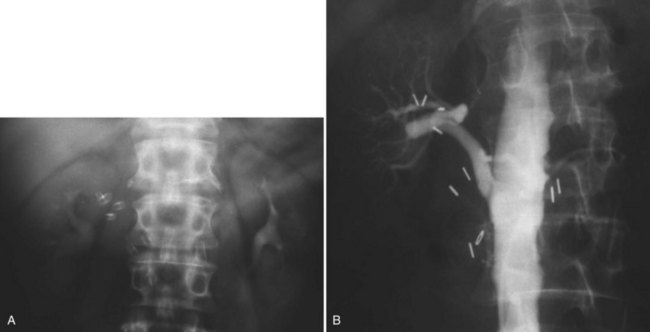

Since its introduction in the early 1970s, renal artery embolization (RAE) has been employed for palliation of inoperable renal tumors, to control bleeding, and as part of multimodal treatment of hypervascular metastatic disease (Almgard et al, 1973). In addition, RAE is used as a preoperative adjunct to resection of locally advanced renal tumors, with or without metastases (Paster et al, 1975) (Fig. 54–15).

Figure 54–15 A, Aortogram in a patient with a left hypervascular renal mass. Note the pooling of contrast medium in the upper pole. B, Left selective artery angiogram before coil placement. C, Aortogram after coil placement demonstrating abrupt cutoff of flow from the left renal artery.

Proposed benefits of preoperative RAE include shrinkage of an arterialized tumor thrombus to ease surgical removal, reduced blood loss, facilitation of dissection due to tissue plane edema, ability to ligate the renal vein before the renal artery at time of nephrectomy, and modulation of the immune response (Klimberg et al, 1985; Bakal et al, 1993; Kalman and Varenhorst, 1999; Schwartz et al, 2007; Wotkowicz and Libertino, 2007; Wszolek et al, 2008). Ligation of the renal vein before the renal artery is useful in the setting of hilar tumors, tumors with significant medial extension, or considerable perihilar adenopathy (Schwartz et al, 2007; Wotkowicz and Libertino, 2007; Wszolek et al, 2008). Before ligating the renal vein, one should characterize the completeness of embolization to prevent unnecessary blood loss in cases of incomplete embolization. In the senior author’s experience this assessment can be made by evaluating renal venous return during surgery. In addition, angioembolization can also be useful for renal tumors associated with large arteriovenous malformations that are having a deleterious hemodynamic impact (Figs. 54-16 and 54-17).

The data regarding preoperative RAE are limited, without any randomized trials evaluating the technique. As a result, in some institutions, surgeons rarely employ preoperative RAE (Boorjian et al, 2007). It is the practice of the senior author to perform preoperative RAE for large renal tumors with hypervascular characteristics or IVC tumor thrombus (Wotkowicz and Libertino, 2007). The ideal timing of nephrectomy after embolization is unclear (Craven et al, 1991; Weckermann et al, 1992; Kalman and Varenhorst, 1999; Schwartz et al, 2007). At the Lahey Clinic, surgery usually is timed 4 weeks after angioinfarction. An imaging study to assess the cranial limit of tumor thrombus is repeated shortly before the operation. Although prospective trials are needed to evaluate the role of preoperative RAE in the treatment of renal cell carcinoma, the senior author has found it a useful preoperative adjunct in the management of locally advanced RCC.